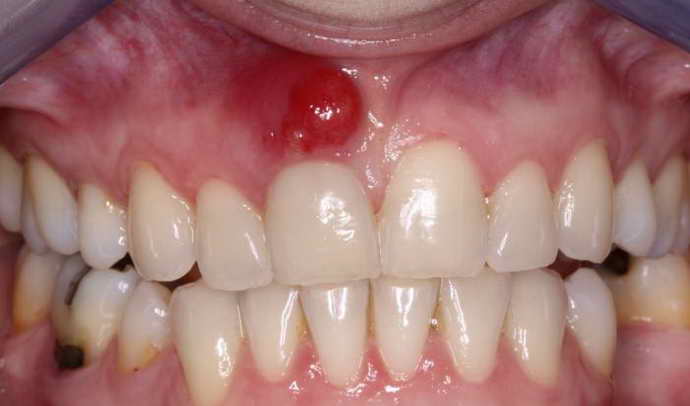

Как выглядит свищ

Различают внутренние фистулы, которые соединяют полости внутри организма, и наружные. Свищ на коже выглядит, как воспаленная рана, из которой сочится гной, края могут напоминать губы (см. фото ниже). Наружная фистула возникает на кожных покровах человека вблизи полостей – например, в области горла и носа. В некоторых случаях человек может не знать о наличии воспалительного процесса в организме, пока на поверхности кожи не появится свищевое отверстие. При тяжелом поражении внутренних органов из канала может выделяться не только гнойный экссудат, но и каловый, мочевой, желчный.

- Гнойные каналы могут возникнуть в любом месте на теле, зачастую они появляются на деснах из-за некачественно залеченного зуба. В редких случаях гнойный свищ может зажить самостоятельно, но чаще наступает рецидив и через канал снова начинает выделяться гнойный экссудат.